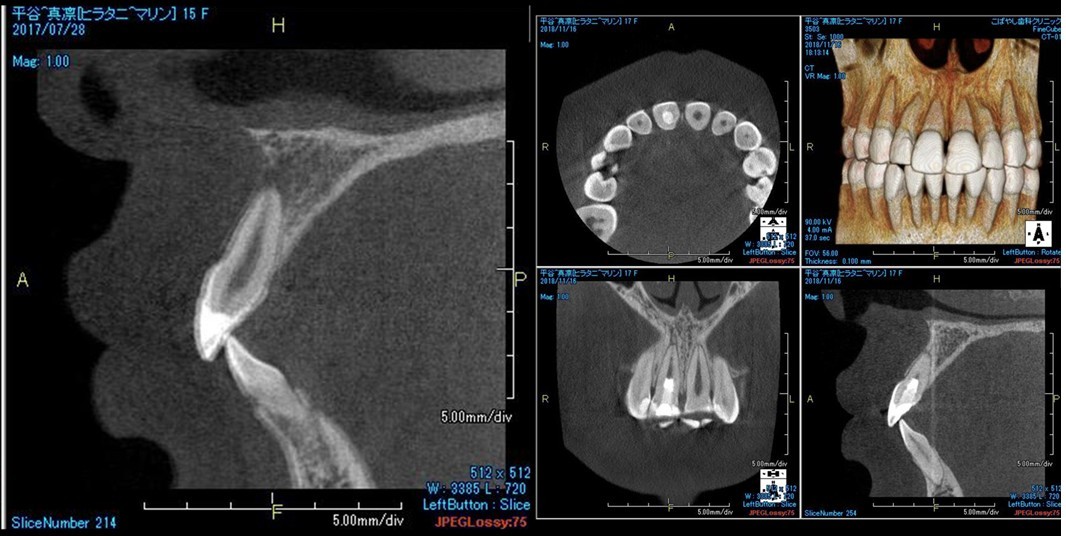

(図32)術後3ヶ月のCBCT像

根尖周囲組織の回復を認める

(図34)初診時と術後3ヶ月のCBCT像の比較

根尖部付近に明らかに変化が認められる特に根尖周囲の骨の回復が確認できる